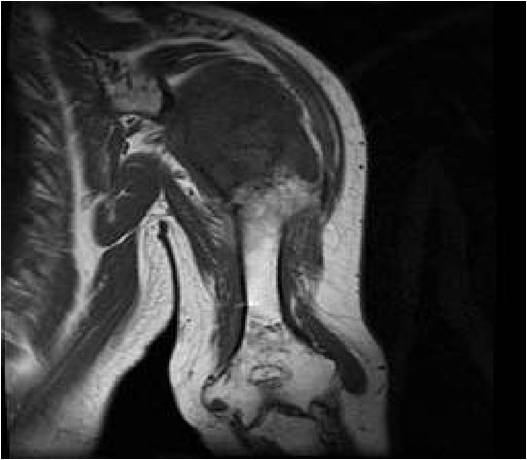

- MRI

- Lobulated margin

- Marked increased intensity long TR images

- Calcified chondroid – low intensity all sequences

MRI:

- Lobulated margin (Lobular Growth Pattern)

- T1 Weighted Images: Intermediate Signal Intensity

- Calcifications will be low signal

- T2 Weighted Images: High Signal Intensity

- High water content shows as high signal on T2 weighted images

- There should never be any cortical destruction nor a soft tissue component. If this exists then the tumor must be a chondrosarcoma.

- Endosteal scalloping and cortical expansion is acceptable for phalangeal tumors. In most benign long bone cartilage tumors there is minimal endosteal scalloping but there should be no cortical expansion nor thickening. There should be no cortical destruction and no soft tissue component associated with an enchondroma. Cortical destruction, periosteal thickening, cortical expansion and a soft tissue component indicates a chondrosarcoma of the long bone.